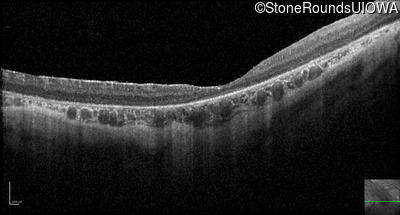

Optical Coherence Tomography - Left - 10/350 sc

Exemplar / OCT Stack